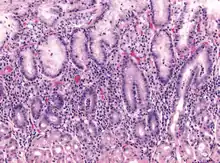

Micrograph showing gastritis. H&E stain.

Early acute superficial gastritis: Marked neutrophilic infiltrates appear in the mucous neck region and lamina with a pit microabscess. This case was caused by Helicobacter pylori.

Acute erosive gastritis typically involves discrete foci of surface necrosis due to damage to mucosal defenses.[18] NSAIDs inhibit cyclooxygenase-1, or COX-1, an enzyme responsible for the biosynthesis of eicosanoids in the stomach, which increases the possibility of peptic ulcers forming.[19][20][21] Also, NSAIDs, such as aspirin, reduce a substance that protects the stomach called prostaglandin. These drugs used in a short period are not typically dangerous. However, regular use can lead to gastritis.[22] Additionally, severe physiologic stress from sepsis, hypoxia, trauma, or surgery is also a common etiology for acute erosive gastritis, resulting in "stress ulcers". This form of gastritis can occur in more than 5% of hospitalized patients.